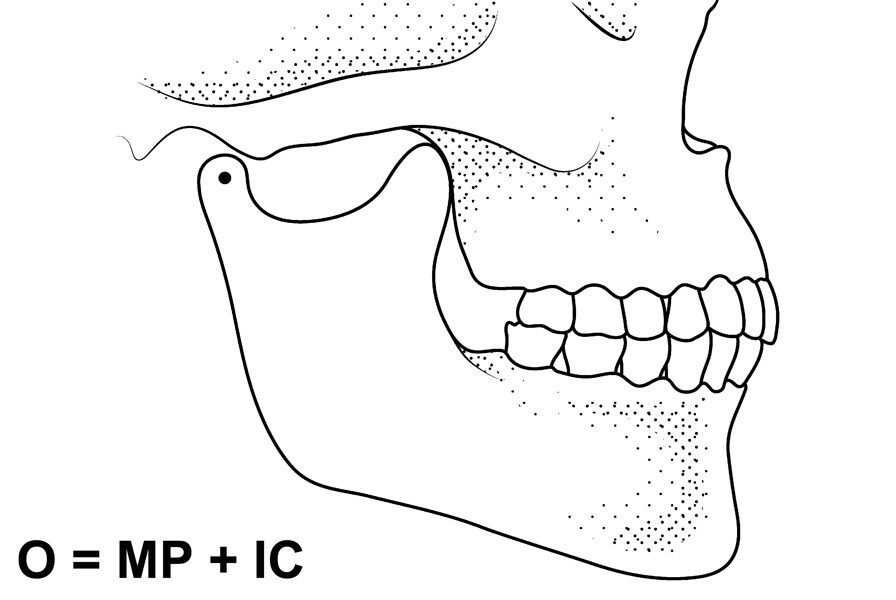

Fig. 2: Mandibular position with condyles down the eminence and maximal intercuspation.

Fig. 5: Occlusion represented as mandibular position and intercuspation.